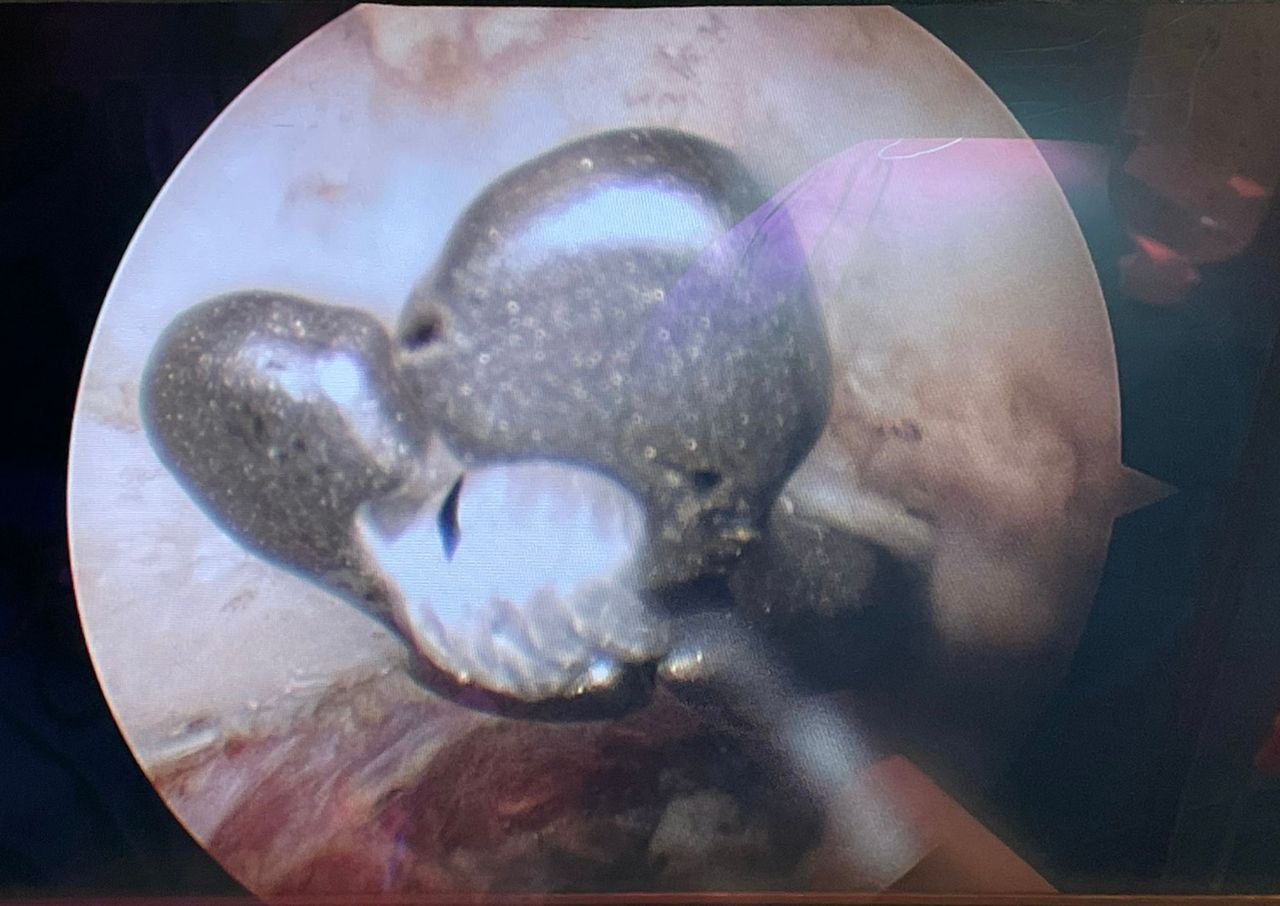

Fotos y vídeos